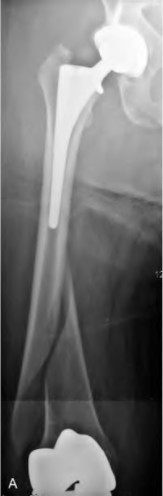

A 78-year-old female sustains a periprosthetic femur fracture 10 years after a cemented THA. Radiographs show a fracture around the tip of the stem with a loose femoral component and poor proximal bone stock, but adequate diaphyseal bone.

What is the most appropriate surgical treatment?